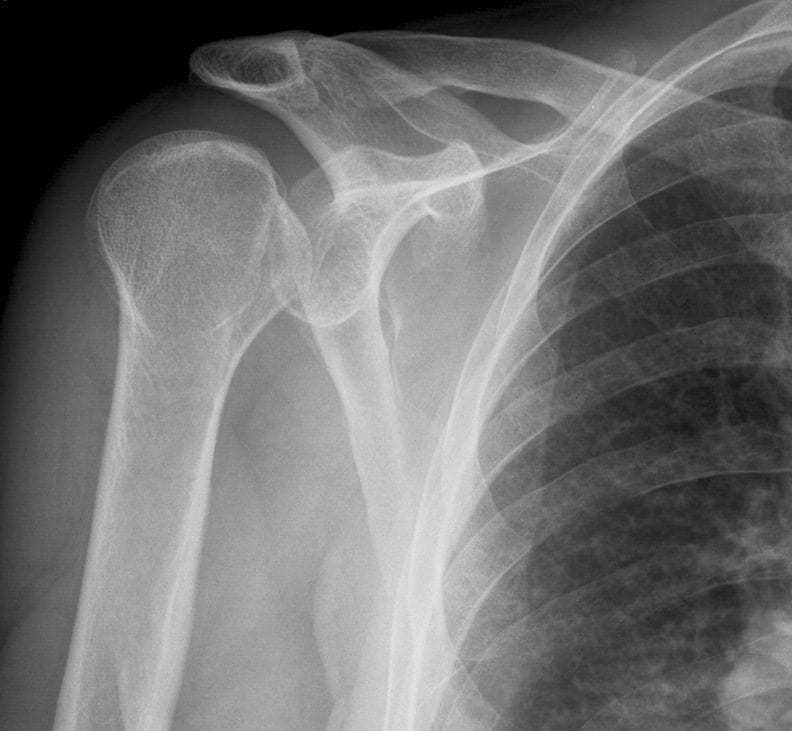

What type of shoulder dislocation does this x-ray show? (AP view)

Posterior shoulder dislocation

Typical X-ray findings in posterior shoulder dislocation include: